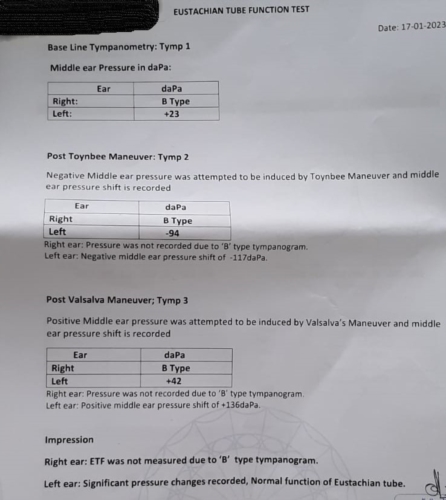

I found an Ent doctor who had performed an Adenoid/tonsillectomy on my daughter. Impressed with the results of that I made an appointment to see if I could get any of my ear symptoms relived and some of my hearing restored. The doctor was sure there was fluid behind the ear drum and that removing it would restore my hearing. He suggested that a T-Tube and balloon dilation would help.

The ENT doctor thought it was chronic inflammation due to Eustachian tube dysfunction and suggested inserting a T-Tube and performing a balloon dilation, I opted out of the balloon dilation due to my occasional patulous eustachian tube (Really the ENT doctor should have flagged this up before recommending it!).

He also recommended turbinate reduction surgery as both turbinates they were enlarged and hypertrophied.

Also, the ear fullness is still there even with a T-Tube inserted, the middle ear pressure should now be equalised with the pressure outside of the ear canal. I wonder whether my TMJ disorder is putting pressure on the eustachian tube? I wear a night guard(splint) to correct my bite but I still wake up with a clenched jaw, so might try one of those anti-snoring tongue devices to try and relax the jaw whilst sleeping.

If after 1 year of no improvement in getting my ET to open, and I have no PET symptoms then I may consider getting the balloon dilation procedure done.